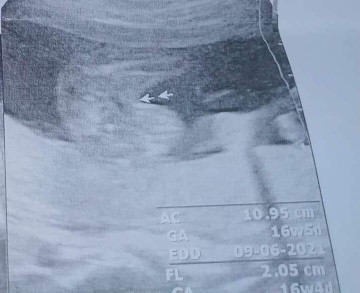

มีบ้านไหนหมอฟันธงว่าเป็นผู้หญิง.. แต่ชอบมีป้าข้างบ้านบอก จริงหรอ.?? ท้องแบบนี้สะดือคว่ำแบบนี้ผู้ชายแน่เลย.. ก็หมอบอกแม่มาแบบนี้😂 ซาวด์เจอตอน 17+2 w น้องอ้าขาให้ดูเลย #แบบนี้มีโอกาสผิดเพี้ยนไหมค่ะ.ตอนนี้21+3w แล้วอิแม่อยากซาวด์ใหม่มากๆ อิแม่เพลียจิต